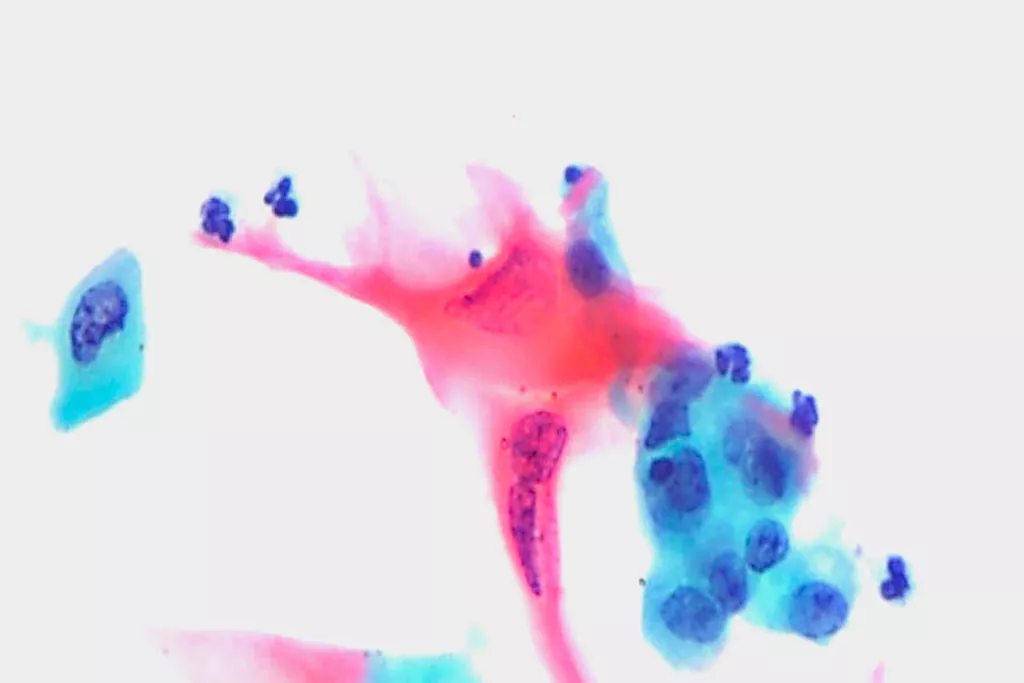

Image Gallery9

9. Images received from Cytopathology Department, Llandough Hospital, Wales